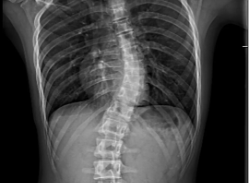

15岁男生重度脊柱侧弯,手术后挺起脊梁迎开学